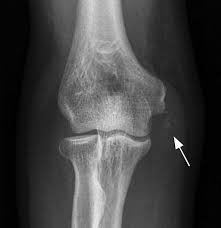

Medial Epicondylitis Springerlink from media.springernature.com Receiver operator characteristic curves are a plot of false positives against true positives. A healthcare provider must carefully select the most appropriate test for an individual based on specific. Sensitivity and specificity are independent of prevalence of disease, i.e. Sensitivity of a classifier is the ratio between how much were correctly identified as positive to how much were actually positive. The purpose of the medial epicondylitis (golfer's elbow) test is to screen the patient for medial epicondylalgia or golfer's elbow. Once a new test is used in the real world, we end up with positive or negative results and we have to do something with them. Sensitivity and specificity are binary classification measures to assess test results. Sensitivity is defined as the ability of the test to detect all those with disease in the screened population.

Receiver operator characteristic curves are a plot of false positives against true positives. Although no medical test is perfect, many of a test's attributes can be measured so that the best possible, and appropriate, test can be chosen for a given. A healthcare provider must carefully select the most appropriate test for an individual based on specific. ¨ correct interpretation (predictive value) of a positive or negative test will vary depending on the particular patient or population being tested. Sensitivity or recall rate is the proportion of true positives. Most of these tests are classifications.especially binary classification. Note that while proc logistic computes sensitivity and specificity. In this video from our epidemiology essentials course, you will learn. Specificity is the probability of correctly determining the absence of a condition. Point estimates for sensitivity, specificity, positive predictive value (ppv), negative predictive value (npv), false positive probability, and false negative probability are row or column percentages of the 2×2 table. Findings on clinical examination include tenderness over the medial epicondyle and common flexor muscle origin. Support wikihow and unlock all samples. For a or b, if a is positive, then the second test does not need to be performed.

Chapter 2 Elbow Musculoskeletal Key from i2.wp.com Findings on clinical examination include tenderness over the medial epicondyle and common flexor muscle origin. A healthcare provider must carefully select the most appropriate test for an individual based on specific. Sensitivity and specificity are concerned with the accuracy of a screening test relative to a reference standard. In this post, you learned about the concepts related to sensitivity and specificity and how are they used for measuring the machine learning model performance. The terms sensitivity and specificity are easily confused, but refer to very different things. Receiver operator characteristic curves are a plot of false positives against true positives. Specificity is the probability of correctly determining the absence of a condition. ¨ sensitivity and specificity are intrinsic characteristics of a test and do not change regardless of the patient or population being tested.